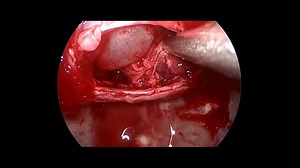

- Pituitary Adenoma

Surgery - Pituitary

Tumor Removal - Pituitary Adenoma

Macroadenoma Surgery - Pituitary

Cyst - Pituitary Tumor Removal